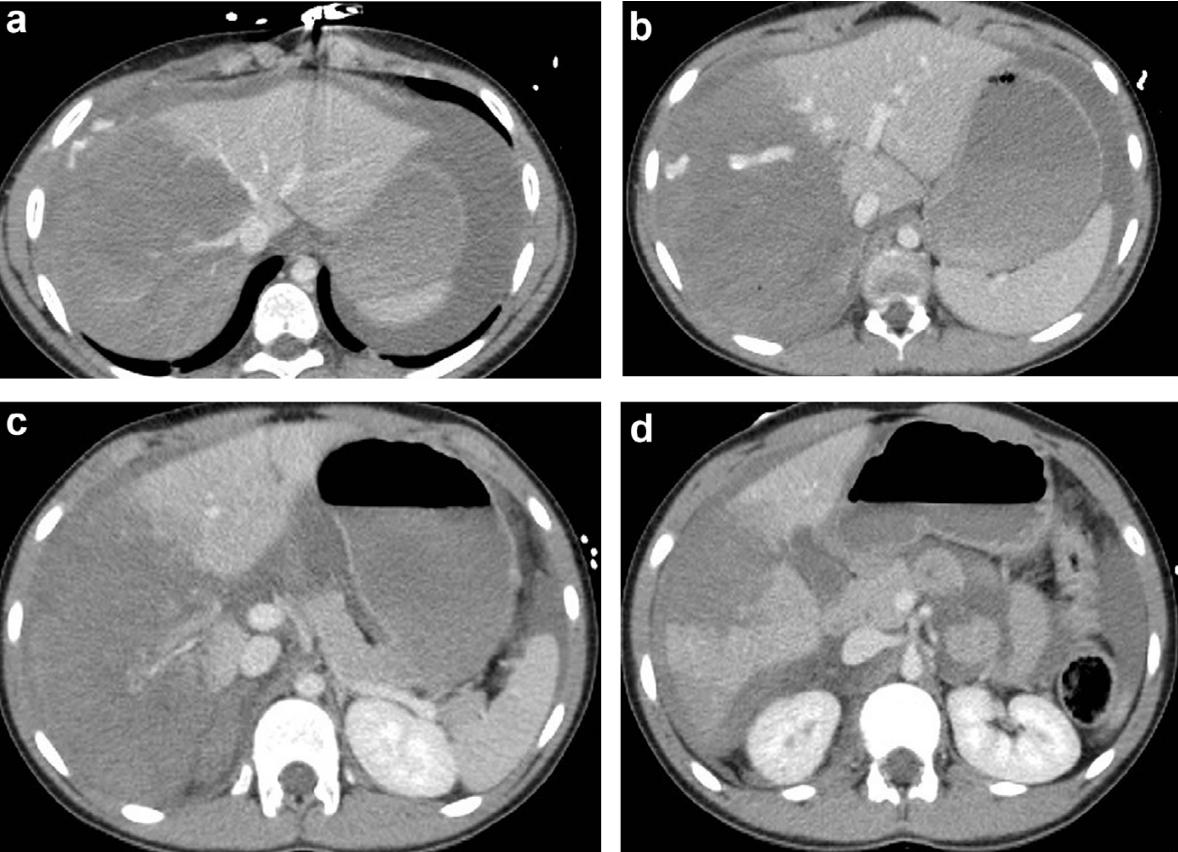

肝脏损伤4度

肝脏损伤介入治疗

5.1. 肝损伤在CT扫描中诊断,从1级到IV级损伤,生命体征稳定,同时:a)损伤未累及肝门。b)肝周血肿比较局限。

- Liver injury diagnosed on CT scan with normalizing vital signs Grade I to IV: a) Injury not into hilum.b) Rim of blood fairly localized around liver.